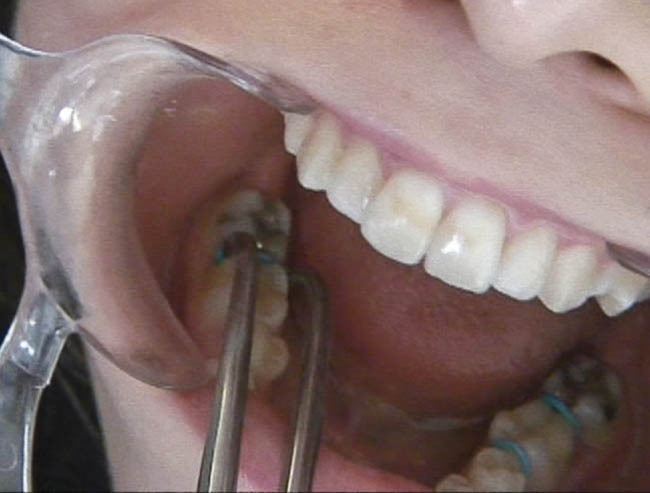

برای قرار دادن سپراتور پلاستیکی نیاز به پلایر سپراتور (شکل 56-1) دارید. سر پلایر را درون یک حلقه کنید و آن را جدا کنید. با فشار پلایر، سپراتور کشیده میشود (شکل 57-1) و به راحتی میتوانید آن را از نقطه تماس رد کنید.

شکل 57-1: نحوه گرفتن پلایر سپراتور